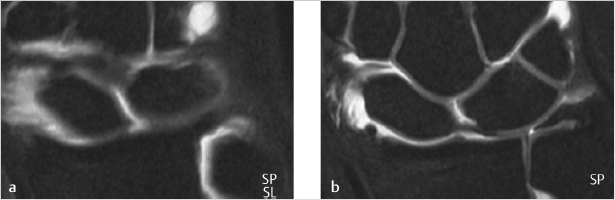

The painful wrist without carpal instability or arthritis can be a diagnostic and treatment challenge. Partial tears of the scapholunate and lunotriquetral interosseous (intercarpal, IC) ligaments and triangular fibrocartilage complex (TFCC) tears can be treatable pain generators (► Fig. 83.1). Simple arthroscopic debridement of these lesions has been suggested to yield successful outcomes with minimal surgical risk.

A thorough understanding of wrist anatomy is essential to enable arthroscopic evaluation of the joint for proper diagnosis and treatment decision making. Careful preoperative decision making and patient selection is critical to a successful result. For the TFCC tears that occur in the vascularized periphery are amenable to repair, whereas those in the avascular center should be debrided (► Fig. 83.2).